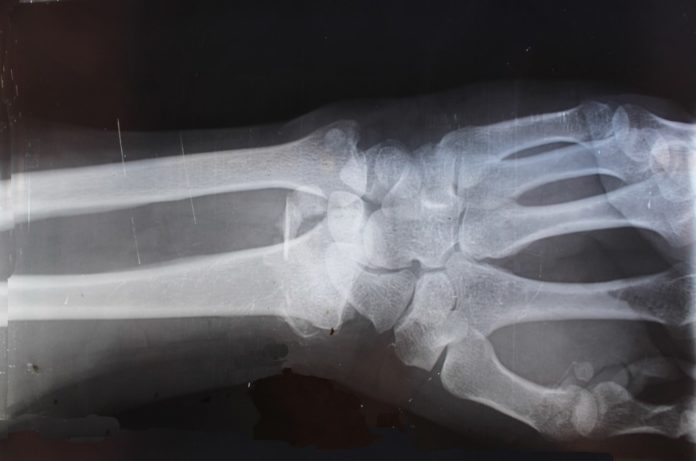

En lo referente a quién debe inyectar esta sustancia, es imprescindible que lo haga un reumatólogo, y siempre tras llevar a cabo las pruebas radiológicas correspondientes. Solo este especialista puede realizar la elección del mejor plan de tratamiento en lo que a contenido de esta sustancia se refiere, y también en lo que respecta a la repetición periódica del tratamiento.